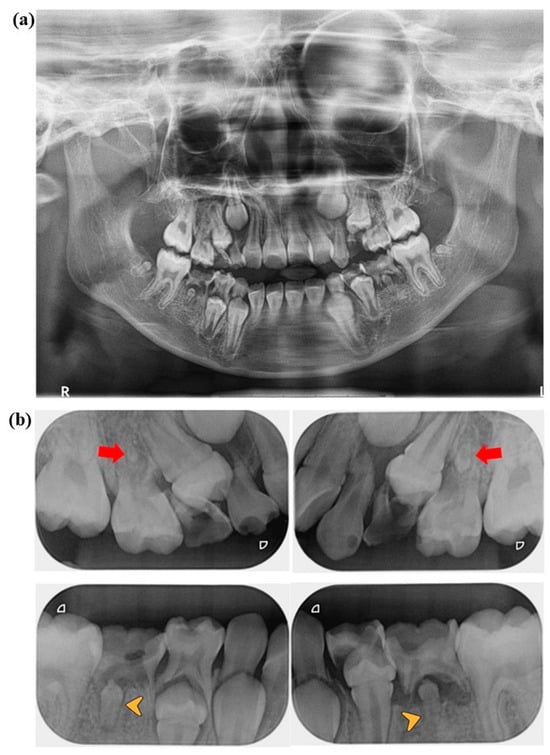

An intraoral and radiographic examination later at the clinic revealed that the patient was in the period of mixed dentition with permanent incisors and first molar present. Figure 1 shows the radiographic images taken during the first dental visit. The decayed-missing-filled-teeth index (DMFT) on permanent teeth was 0. The primary molars and canine teeth exhibited poor oral hygiene, with a DMFT of 10 on the primary teeth, as shown on a standard panoramic radiograph (Figure 1a) and periapical radiographs (Figure 1b). Extensive destruction of teeth and pathological changes in the regions surrounding the tooth roots of tooth numbers 54, 64, 74, 75, and 85 were diagnosed as pulp necrosis with chronic apical periodontitis. Carious lesions in the dentin area of tooth numbers 53, 63, 65 and 84 were diagnosed as dental caries. Additionally, a carious lesion in the enamel area of tooth number 55 was diagnosed as enamel caries. The dental treatment plan involves tooth removal, restoration with composite filling, and a stainless-steel crown under local anesthesia, which are all invasive (bleeding) procedures.

Figure 1. (a) Panoramic radiograph and (b) periapical radiographs were taken of the 7-year and 4-month-old patient (first visit). The film shows the patient’s primary teeth with a decayed-missing-filled-teeth index (DMFT) of 10. (b) The red arrows show rudimentary formations on tooth numbers 15 and 25. The yellow arrow heads show microdontia on tooth numbers 35 and 45.